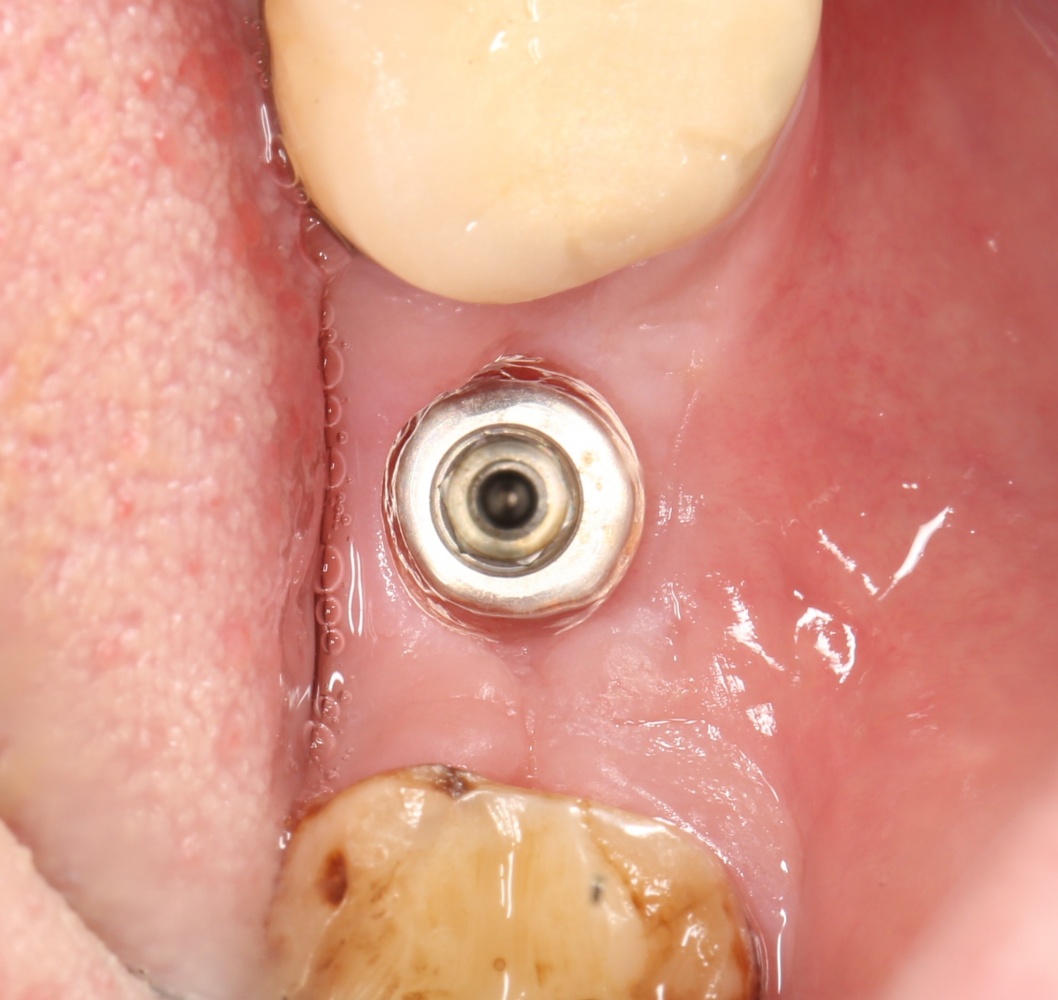

Рекомендации по установке имплантов. Для всех. Часть V.